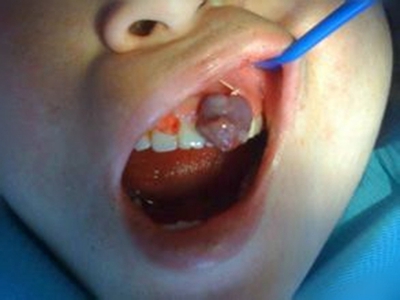

肿块有的有蒂,如息肉状;有的无蒂,基底宽广,生长较慢,但在女性妊娠期间可能迅速增大。较大的肿块可以遮盖一部分牙及牙槽突,表面可见牙压痕,易被咬伤而发生溃疡,伴发感染。随着肿块的增长,牙槽骨壁逐渐被破坏,牙可能发生松动、移位。

对于牙龈瘤可在局麻下手术切除,切除必须彻底,否则易复发。如果复发,仍可手术切除。多次复发者,即使病变波及的牙无松动,也应将牙拔除,防止再发。